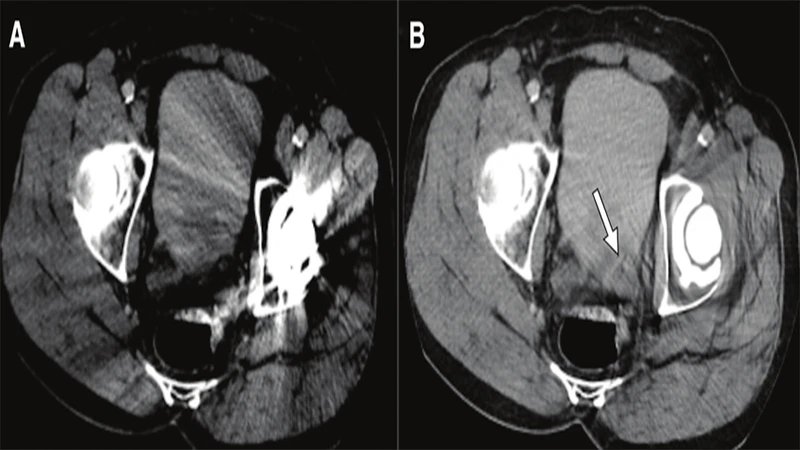

2. Metal Artifact

Metal objects on or inside the patient can severely distort the image, particularly in CT and MRI.

• Appearance (CT): Severe streaking or "starburst" patterns originating from the metal object.

• Appearance (MRI): Large, dark signal voids with bright, distorted edges. The distortion is often much larger than the object itself.

• Cause: High-density metal (like dental fillings, surgical clips, or joint replacements) completely absorbs X-rays in CT. In MRI, ferromagnetic metals distort the local magnetic field.

• Solution:

• Screening: The best solution is prevention. Thoroughly screen patients for removable metal (jewelry, piercings, clothing).

• Positioning: If possible, position the patient so the metal is outside the primary area of interest.

• Software: Modern scanners have dedicated Metal Artifact Reduction Software (MARS) algorithms that can help correct the image during reconstruction.

A CT scan of a pelvis with a hip replacement, showing severe streaking artifacts obscuring nearby anatomy.